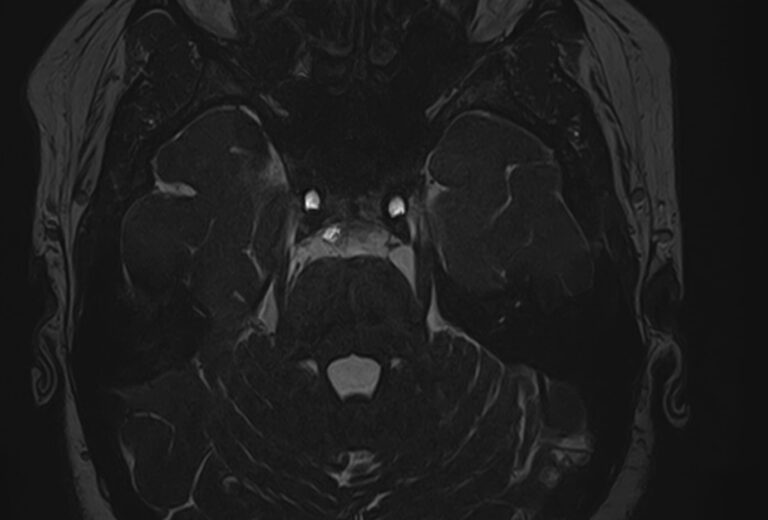

Для диагностики поражения черепно-мозговых нервов, а также оценки состояния окружающих их тканей и визуализации сосудистой сети головного мозга в клинике «Доступная медицина» проводится комплексное обследование МРТ головного мозга + черепно-мозговые нервы. Данное обследование включает в себя 2 протокола: стандартный — для оценки состояния всех структур головного мозга и специализированный — для изучения очагов поражения черепных нервов.

Оба исследования выполняются на современном высокопольном томографе экспертного класса TOSHIBA VANTAGE TITAN 1,5 Тесла, который использует разные режимы сканирования с толщиной среза от 1мм в различных плоскостях с последующей цифровой обработкой полученных данных для создания трехмерных изображений. Аппарат позволяет выявлять структурные изменения в веществе головного мозга и черепных нервах уже на начальной стадии, когда другие методы не дают результатов.

• патология нервов на фоне сосудистых проблем (вазоневральный конфликт — сдавление нерва близлежащим сосудом, также на фоне патологической извитости, аневризмы, сосудистой мальформации).